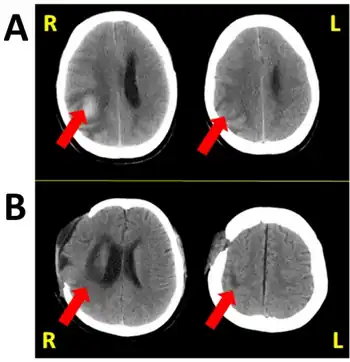

a,b) Hemispatial neglect -image showing stroke sites in the two cases